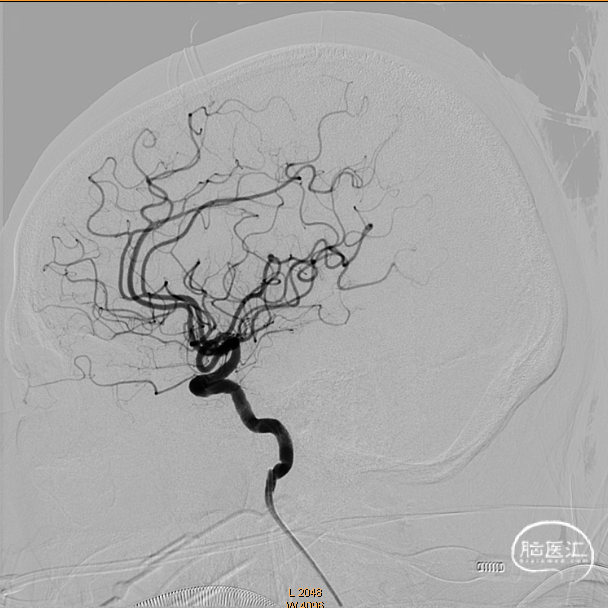

术前影像学资料

造影证实右侧颈内动脉闭塞。

左侧正侧位造影。

后循环造影。